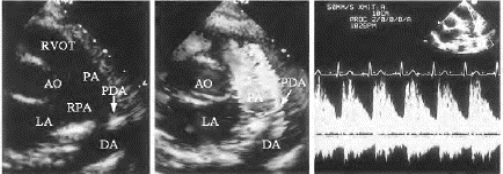

图16-10 动脉导管未闭超声图

左图:2D心底短轴切面示左肺动脉基部回声失落(↓),主肺动脉与胸主动脉相通;中图:同左图切面,红色为主彩色血流(↙)自胸主动脉(DA)经导管进入主肺动脉的分流血流束,沿主动脉左侧上行(见彩图20);右图:CW显示正向、连续性以收缩期为主的分流血流频谱